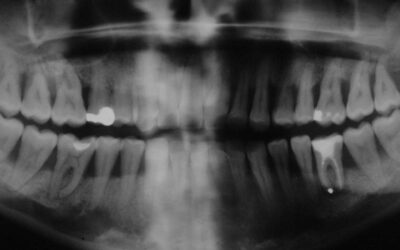

Durch Fistelung komplizierter, kombiniert endodontisch-parodontologischen Fall, wie er täglich vorkommt und genau so regelmäßig zur Extraktion gelangt. Dabei ist ein solcher Befund mit Geduld sehr einfach und routinemäßig auszuheilen.Deutlich sieht man die abgefüllte...